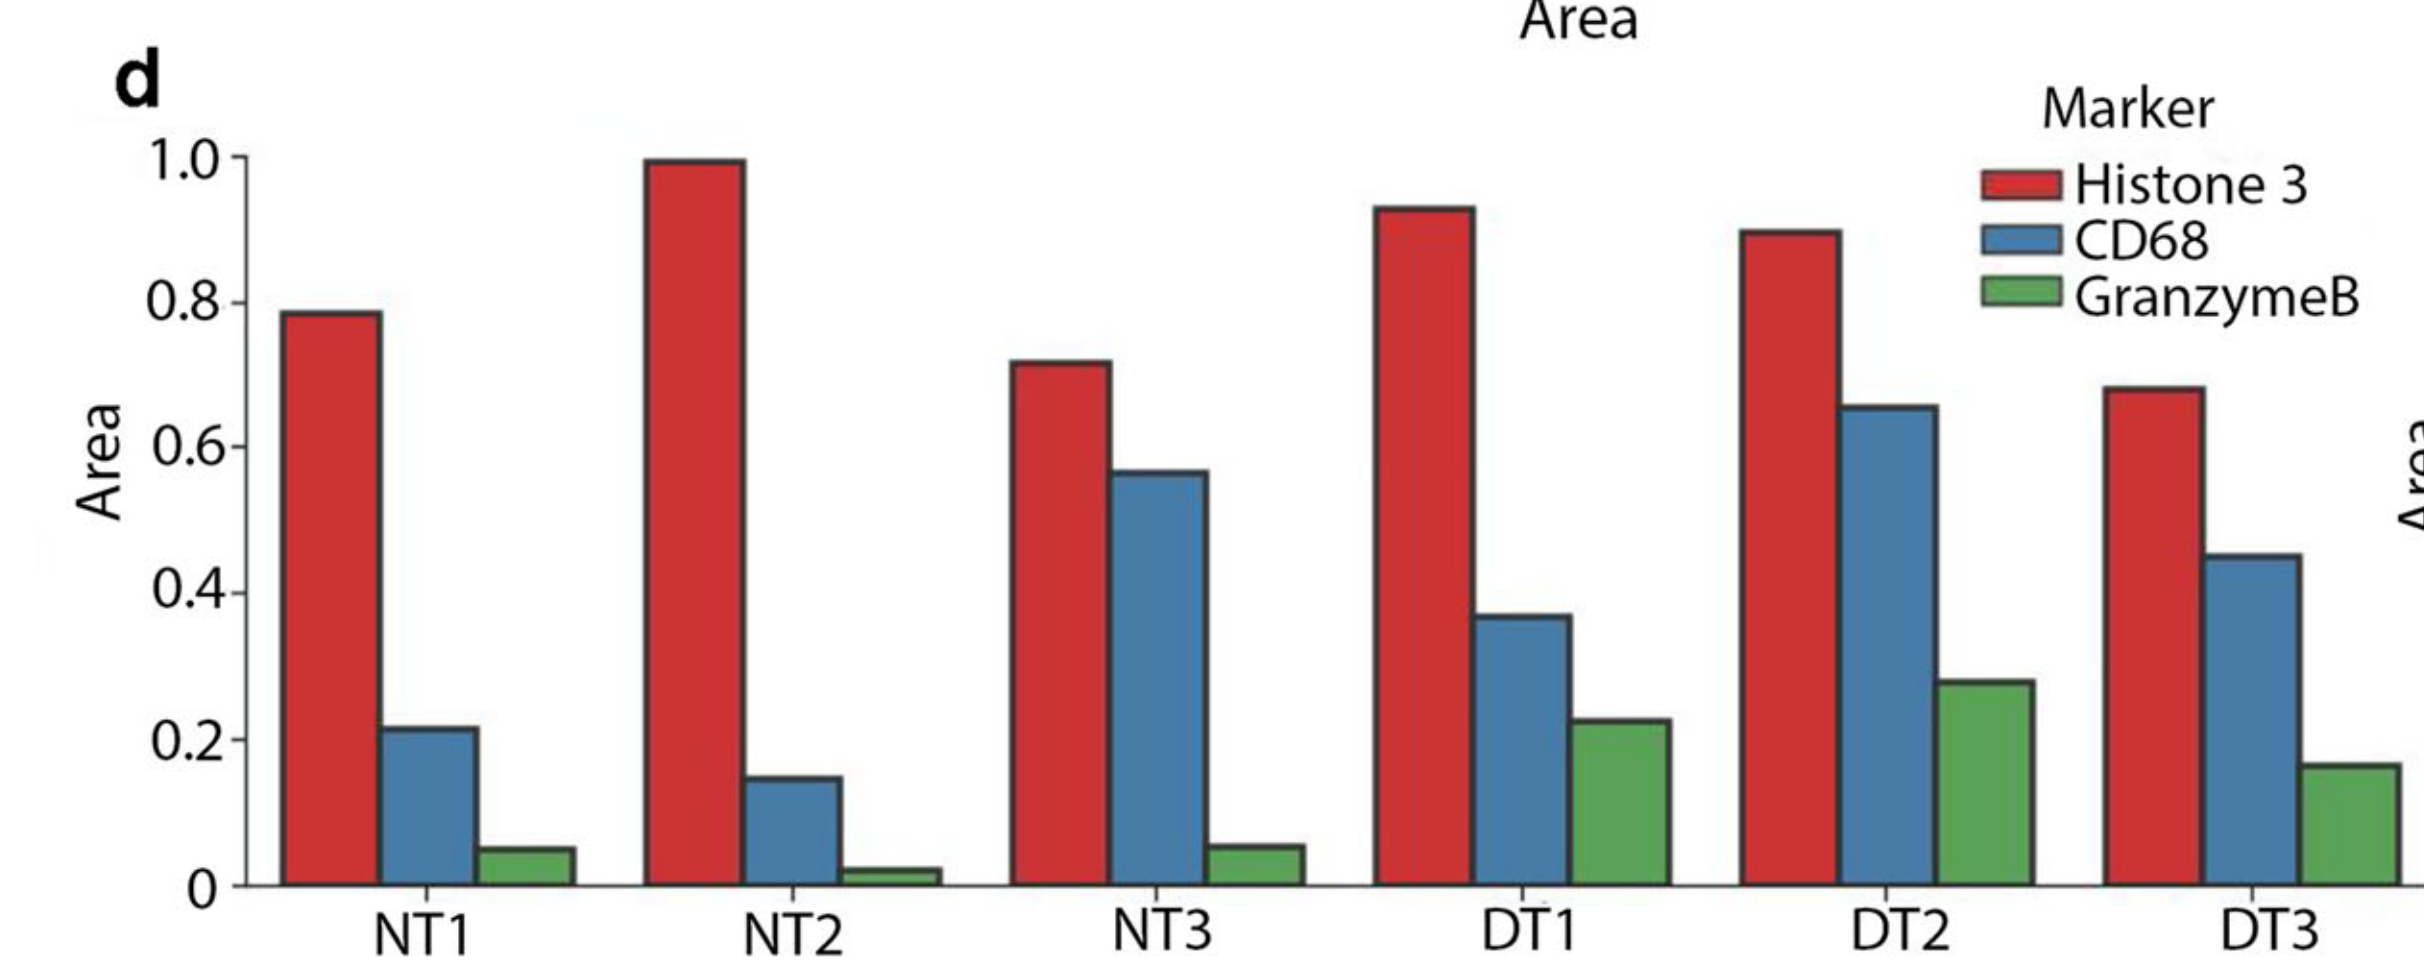

Li X. et al. - 2025

SPEX: A modular end-to-end platform for high-plex tissue spatial omics analysis

Condition Dimension

Categorical

Data Components

Biological AnnotationGene Expression Matrix

Metadata

None

Modality

Proteomics

Resolution of observation

Cellular

Visualized Elements

Statistic

How does expression of a gene differ across patient categories?

Biological

Molecular

Abstraction

Complete

Chart Type

Boxplot

Communicative/Contextualization

Annotation

Comparative Design

Juxtaposition

Layout

Linear

Scalability Strategy

Summay/Aggregate